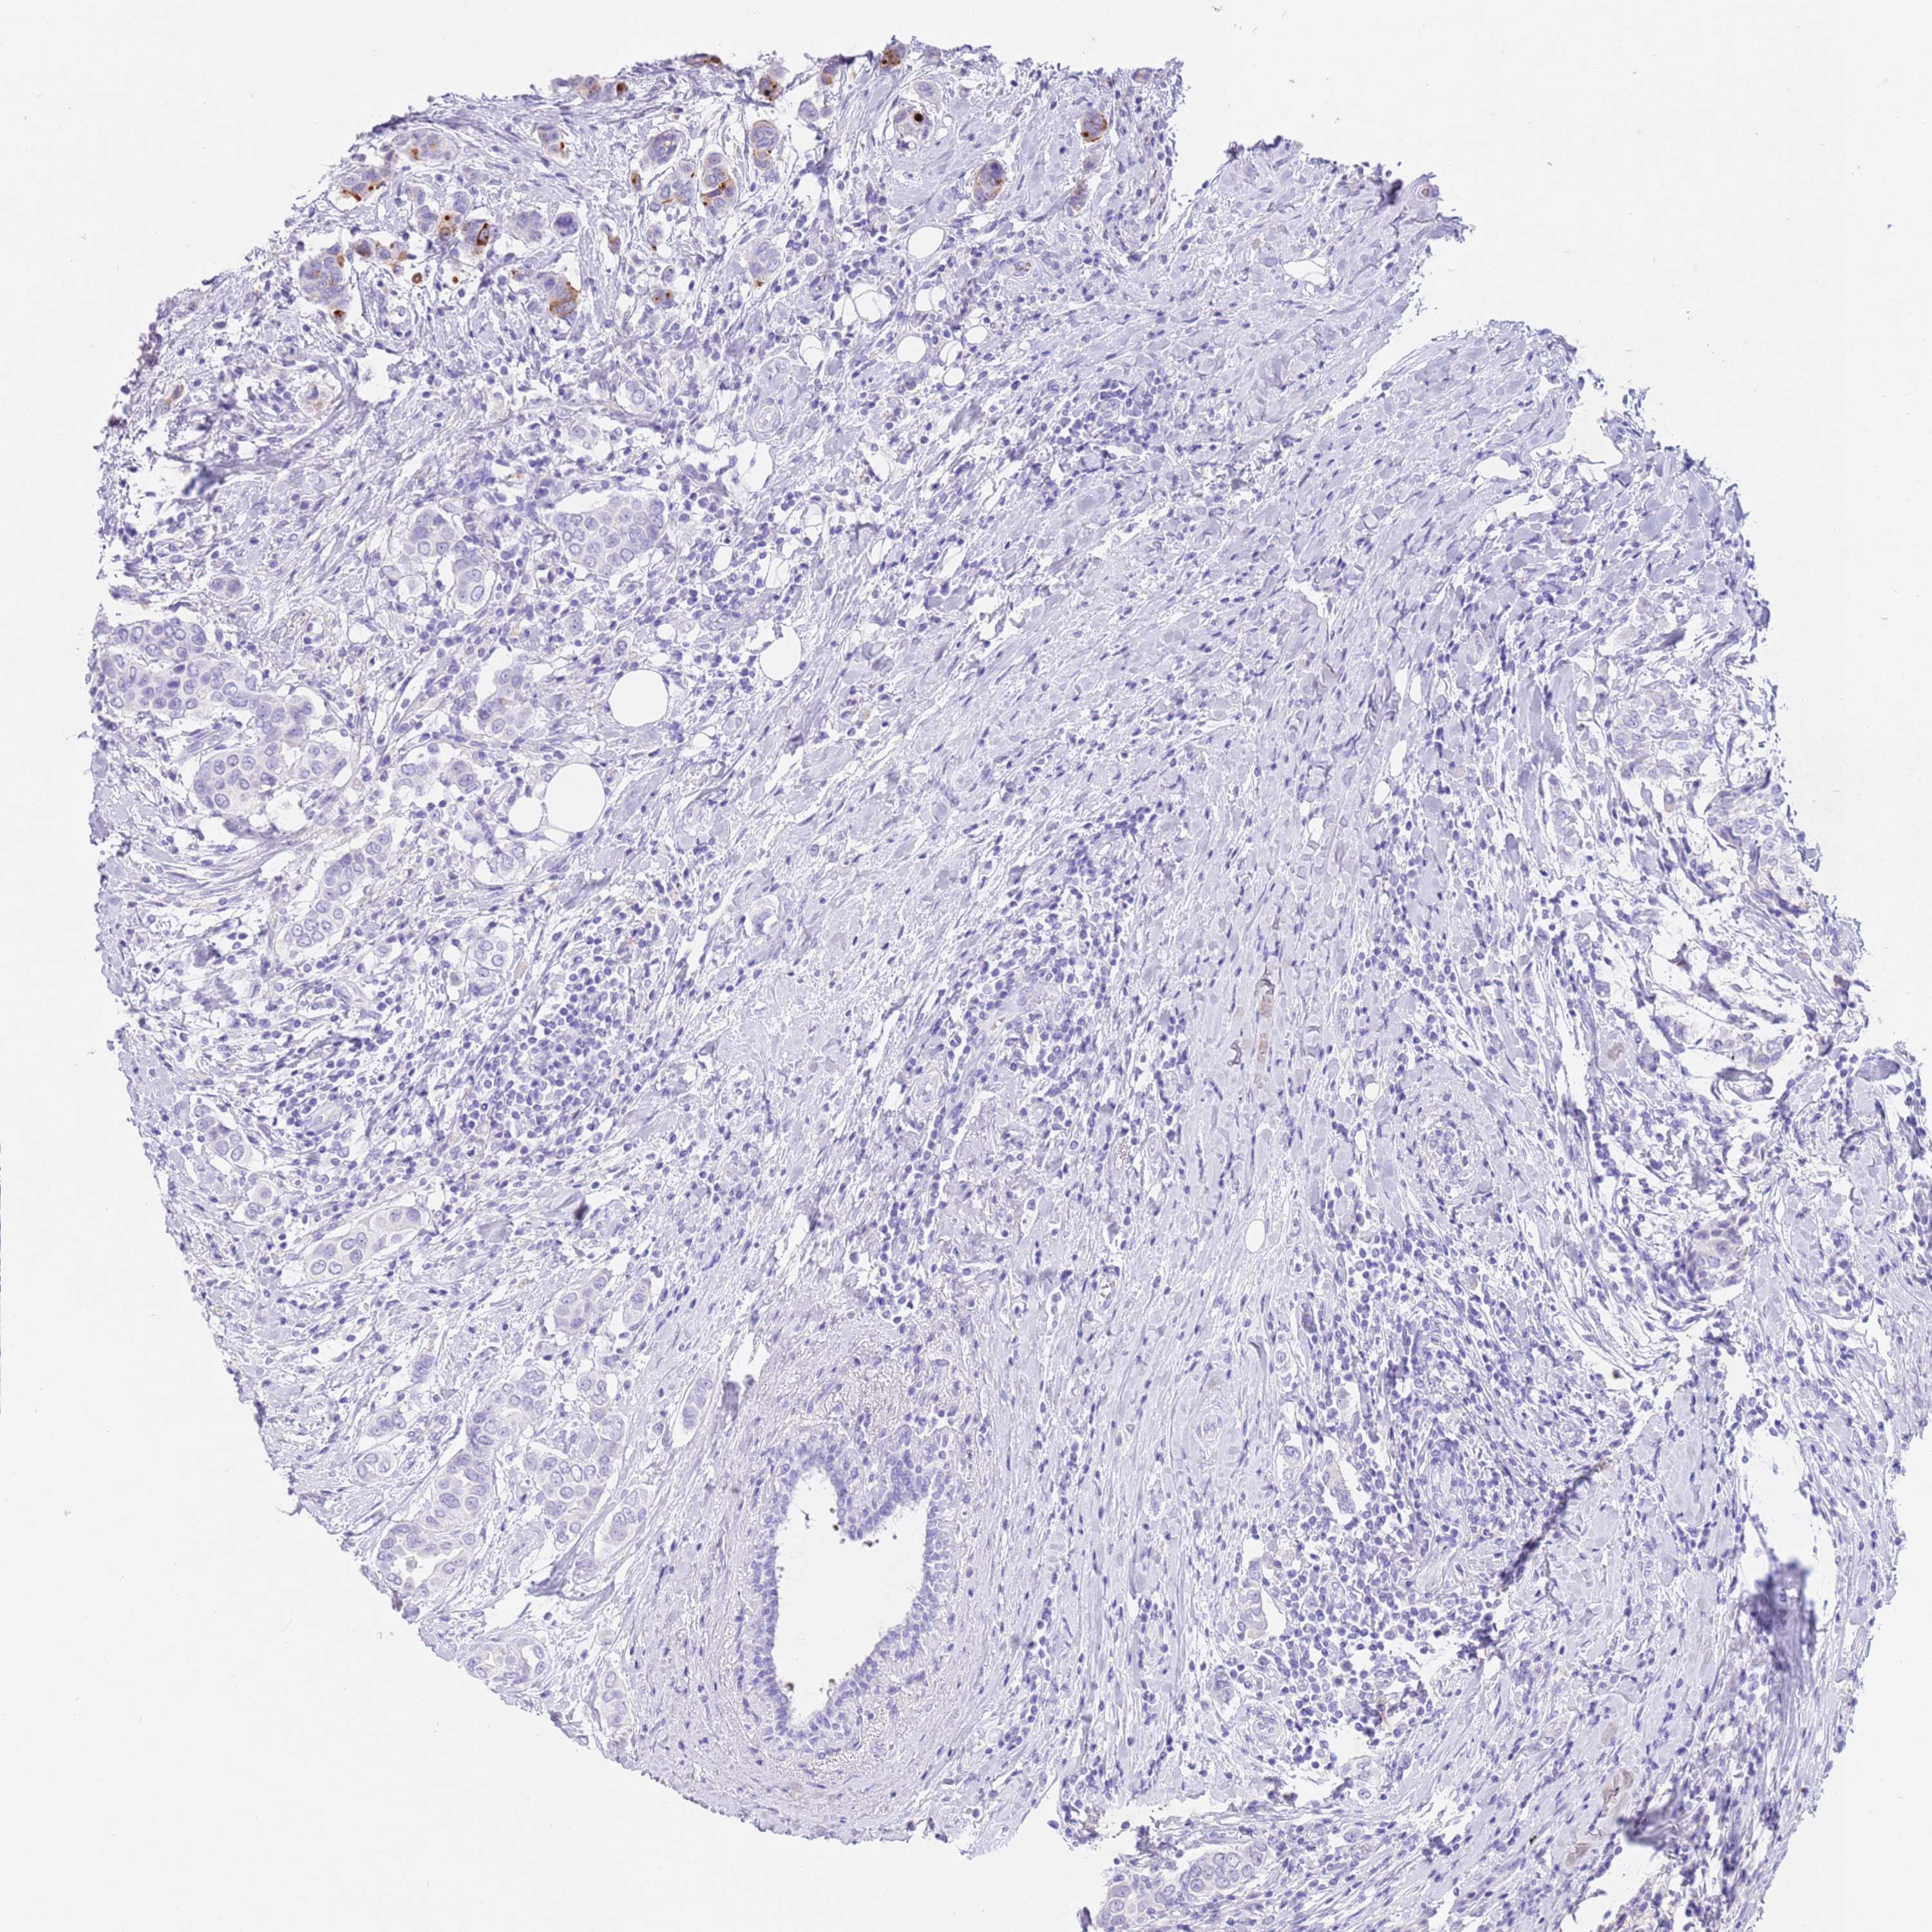

CANCER BREAST CANCER Show tissue menu

BRCA TCGA BRCA VALIDATION PROTEIN EXPRESSION

ANTIBODIES

AND

VALIDATION